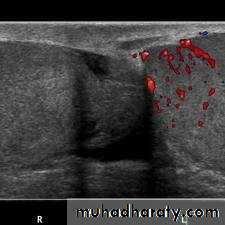

torsion of a testicular appendage.Color Doppler ultrasound .

Epididymoorchitis.

radionuclide scanning .